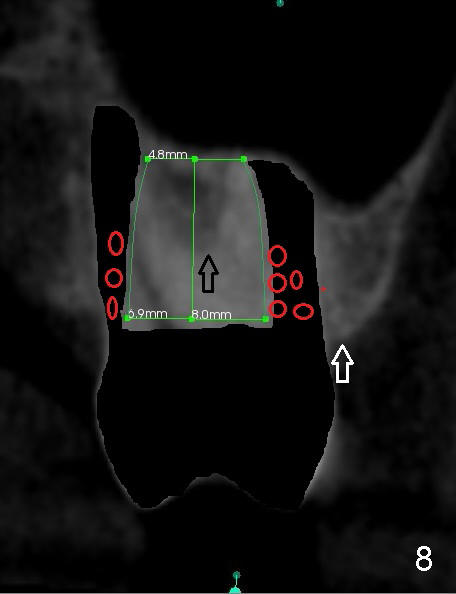

When the buccal roots are fused, there are 3 potential sites for immediate implant (Fig.1'): septum (*), buccal (B) and palatal (P) sockets. Septal placement (6.9x8 mm bone level implant) is the most ideal for restoration (Fig.3). The length of the implant can be increased (10 mm) with sinus lift so that the base of the implant between the buccal and palatal apices in height (Fig.4). Primary stability is derived mainly from the implant body engagement into the septum (Fig.5 coronal section through the septum). If bone density in the septum is high, a small implant may be appropriate (Fig.6,7: 6.4x8 mm). The large implant (6.9 mm) is chosen so that amount of bone graft to be used (Fig.8 red circles) is less.